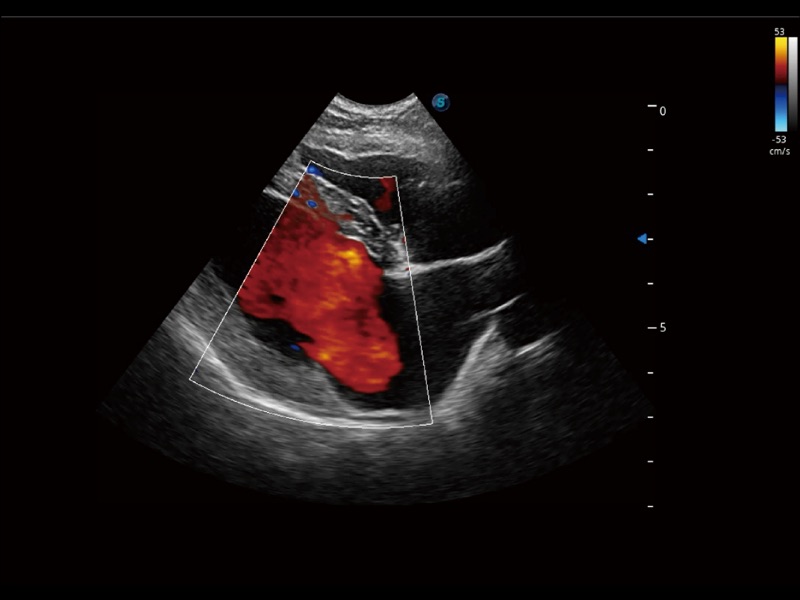

采用红、橙、黄、绿、青、蓝、紫这七种肉眼最为敏感的色彩,直观地显示组织内血流灌注的时间先后信息,更精准捕捉血流灌注走行细节。

能够基于左心室壁追踪和辛普森法,自动计算射血分数,支持多个可移动点描迹,与手动测量相比,极大节省了动物医生的时间和精力。